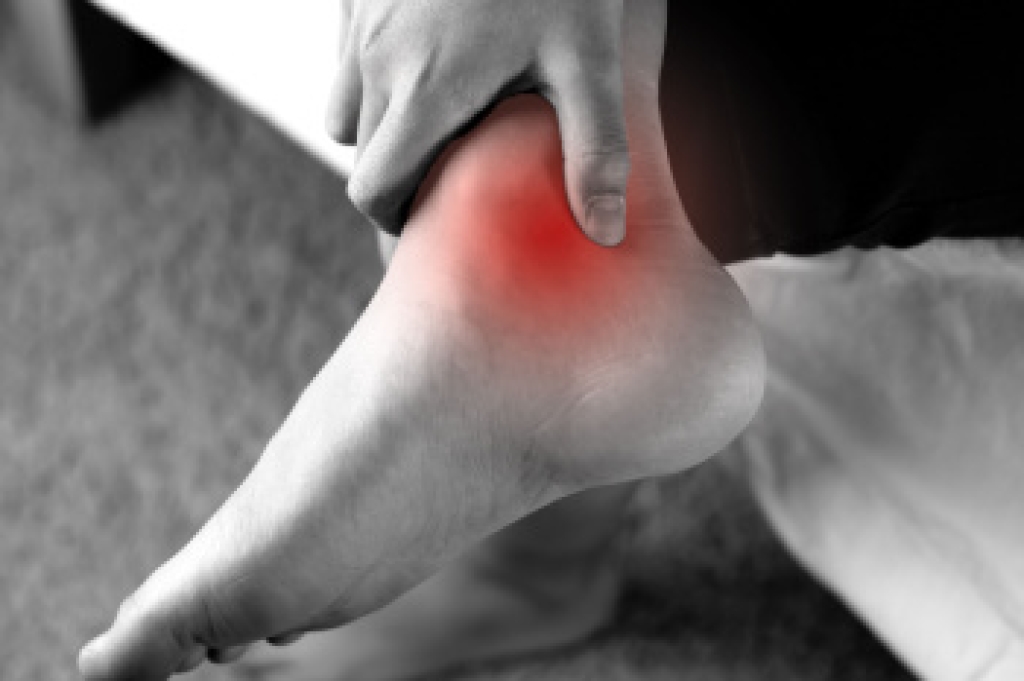

Plantar fasciitis is a common condition that causes pain in the heel and bottom of the foot. The primary cause of plantar fasciitis is repeated stress or strain on the fascia, often due to excessive walking, running, or standing. Other factors like wearing poor footwear, tight calf muscles, or being overweight can also contribute. The most noticeable symptom is sharp pain in the heel, especially when taking the first steps in the morning or after periods of rest. As the day progresses, the pain may lessen but can return with prolonged standing or walking. Diagnosis typically involves a physical examination where a podiatrist may palpate the heel and foot, and sometimes imaging tests to rule out other conditions. If you have heel pain, it is suggested that you contact a podiatrist who can accurately diagnose and treat plantar fasciitis.

Plantar fasciitis is one of the most common causes of heel pain. The plantar fascia is a ligament that connects your heel to the front of your foot. When this ligament becomes inflamed, plantar fasciitis is the result. If you have plantar fasciitis you will have a stabbing pain that usually occurs with your first steps in the morning. As the day progresses and you walk around more, this pain will start to disappear, but it will return after long periods of standing or sitting.

There are some risk factors that may make you more likely to develop plantar fasciitis compared to others. The condition most commonly affects adults between the ages of 40 and 60. It also tends to affect people who are obese because the extra pounds result in extra stress being placed on the plantar fascia.